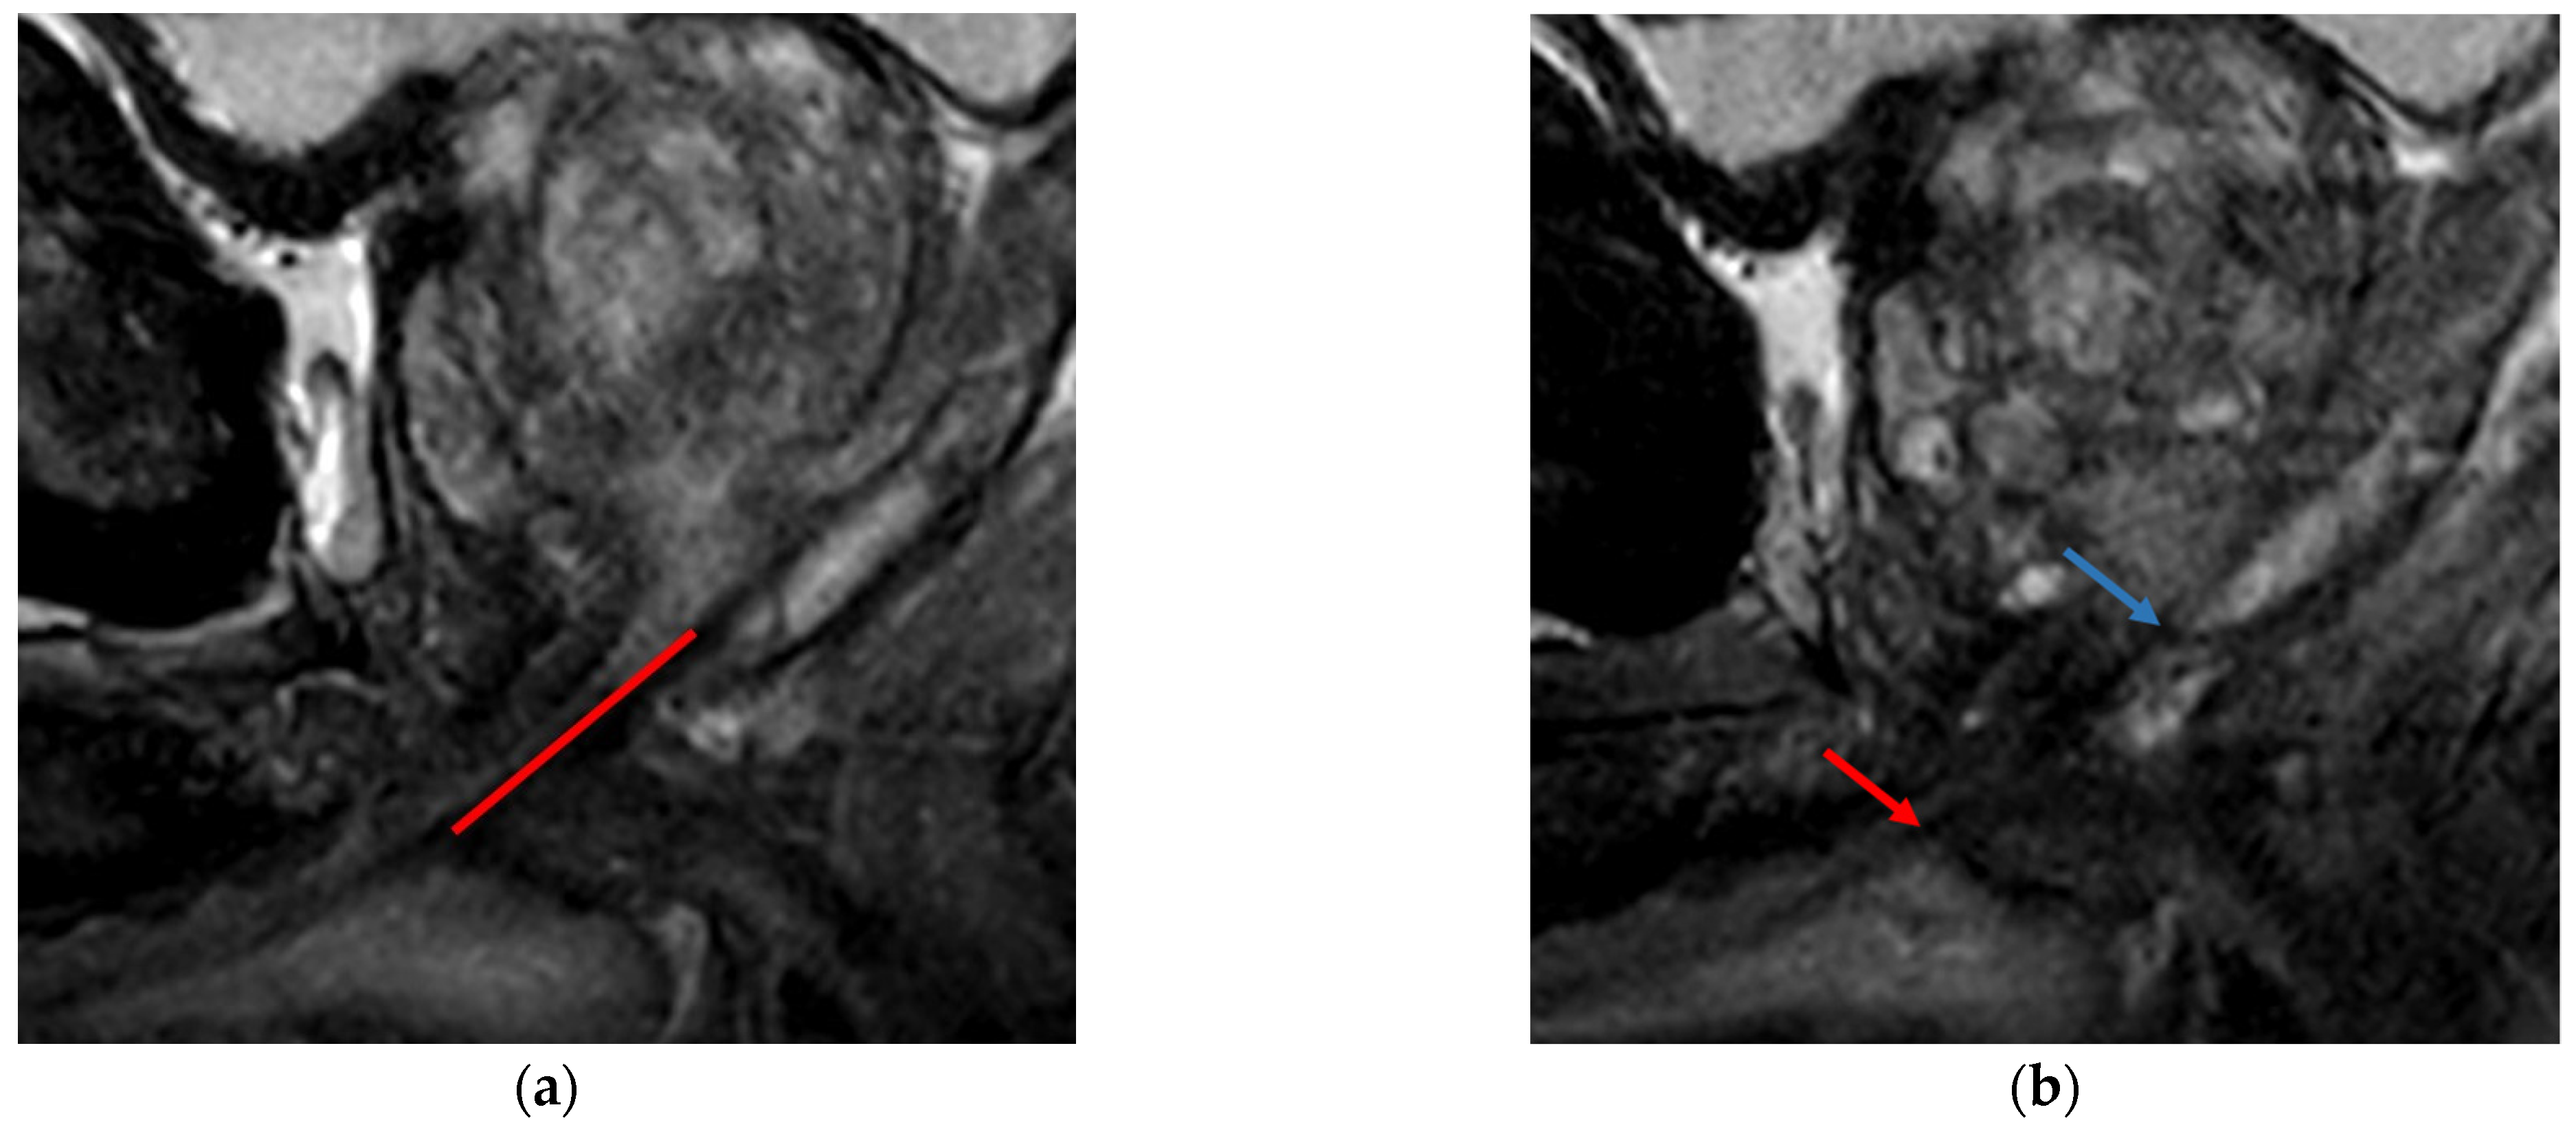

- Veerman, H.; Hagens, M.J.; Hoeks, C.M.; van der Poel, H.G.; van Leeuwen, P.J.; Vis, A.N.; Heijmink, S.W.T.J.P.; Schoots, I.G.; de Haan, M.C.; Boellaard, T.N. A standardized method to measure the membranous urethral length (MUL) on MRI of the prostate with high inter- and intra-observer agreement. Eur. Radiol. 2022. [Google Scholar] [CrossRef]